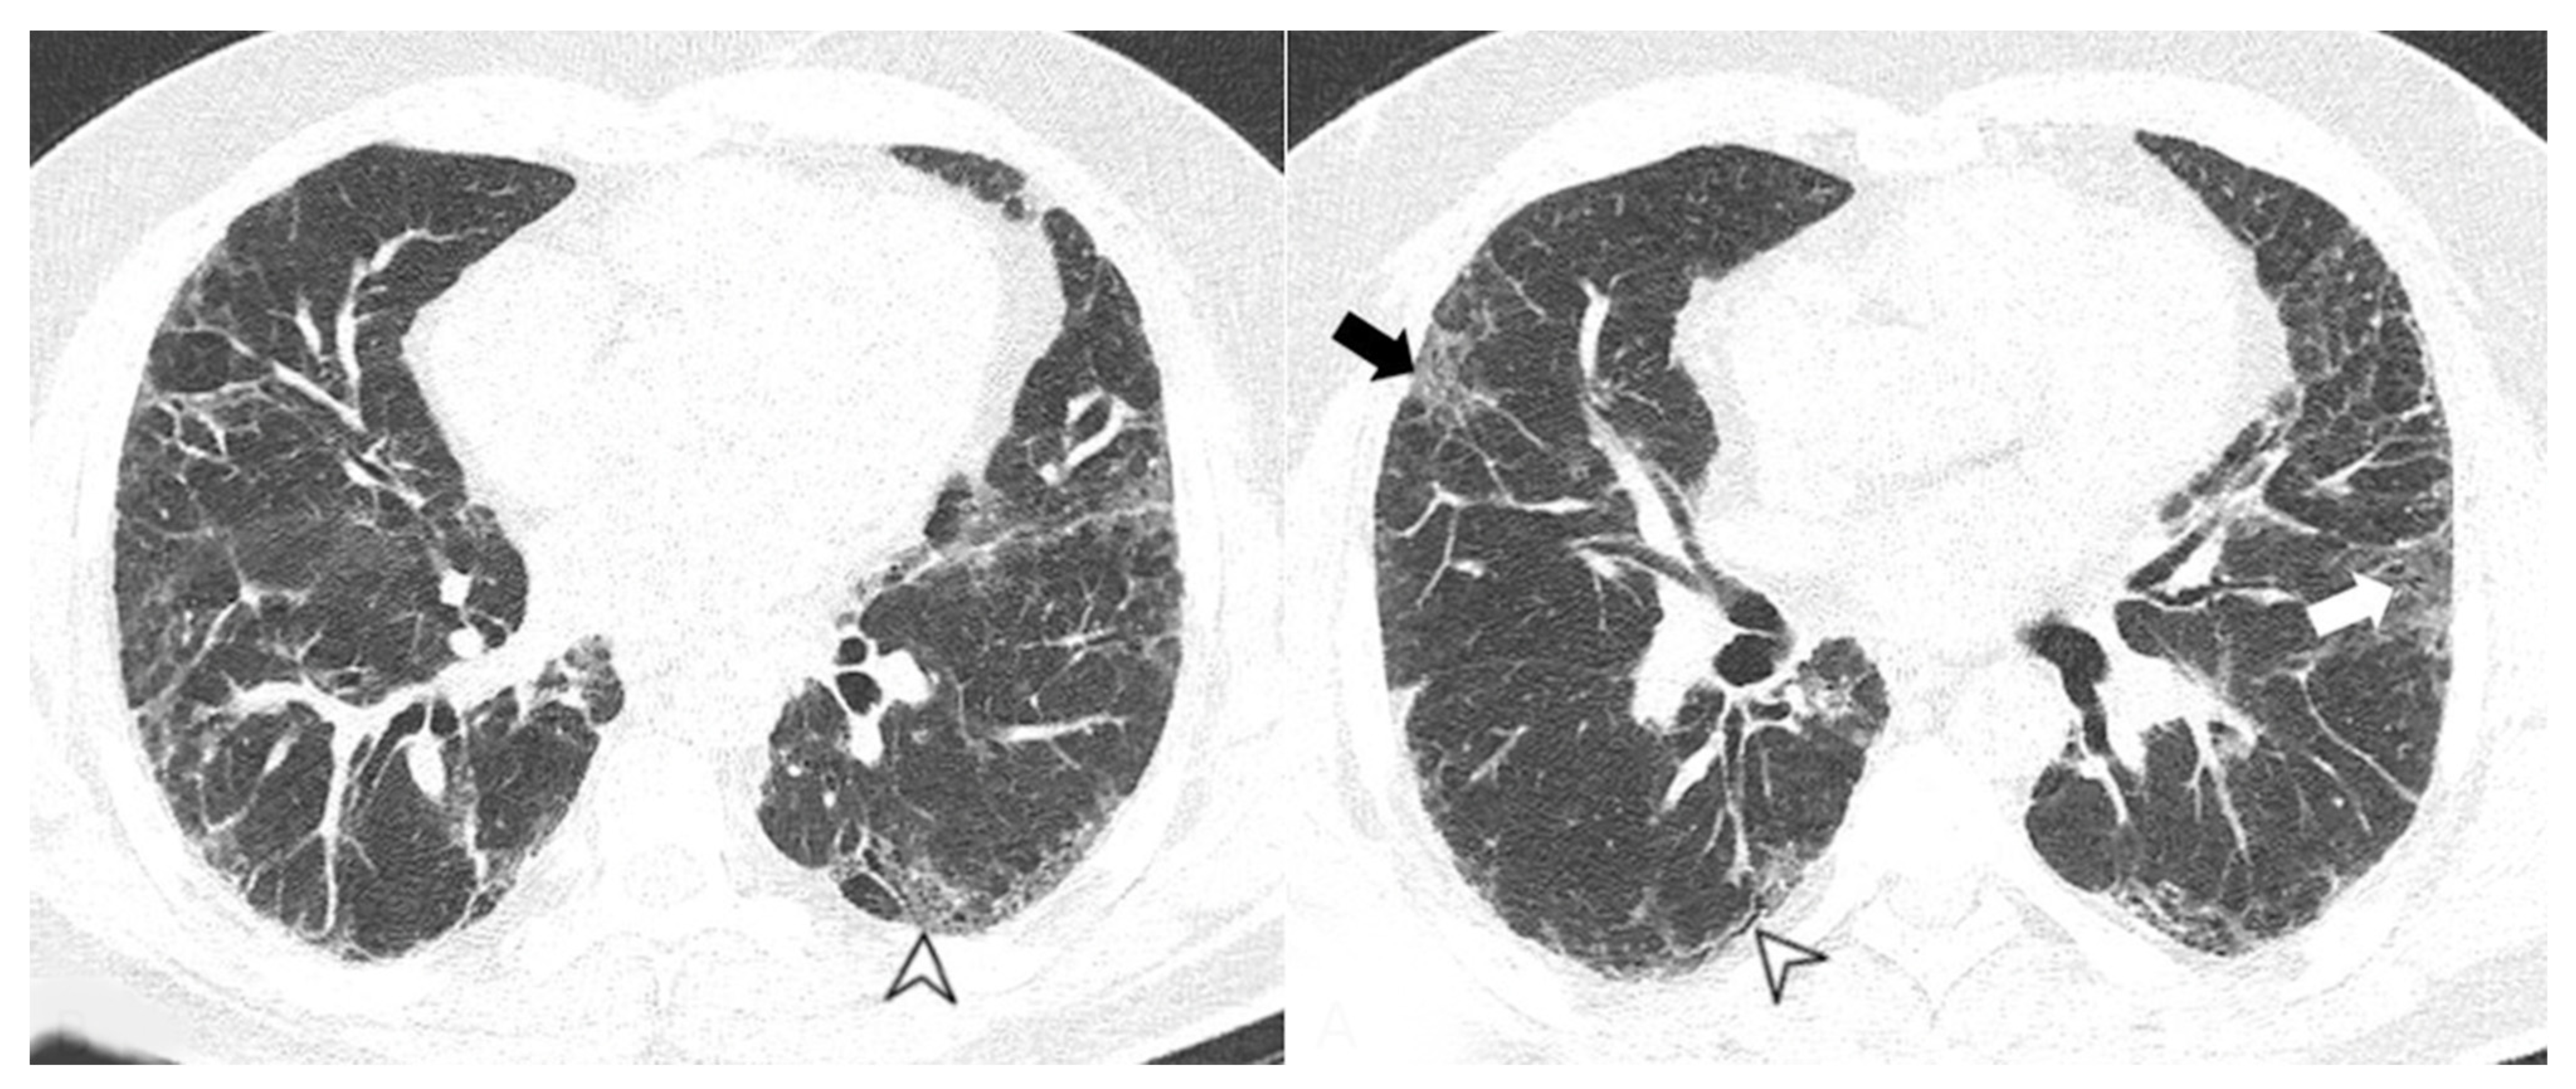

- Chronic progressive fibrosing ILD (reticulation and honeycombing with minimal GGOs on HRCT scans, related to fibrotic NSIP or UIP) [43];

| Lesions | GGO, reticulations, consolidations | consolidations, GGOs | |

| Distribution | Homogeneous; lower lung lobes, along bronchovascular bundles and lung periphery; loss of volume of lower lobes | Patchy; peripheral lower lobes or along the bronchovascular bundles | |

| CT pattern | NSIP OP NSIP-OP UIP DAD-unclassifiable | 50% 20% 25% 10% +/− | 20% 50% 25% <5% ++ |